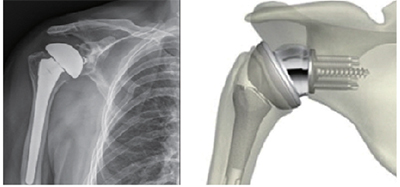

어깨관절인공관절치환술

• 어깨 관절의 손상도가 큰 경우 어꺠 관절의 통증을 줄여주고 더 이상의 진행을 막을 인공관절치환술이 필요합니다.